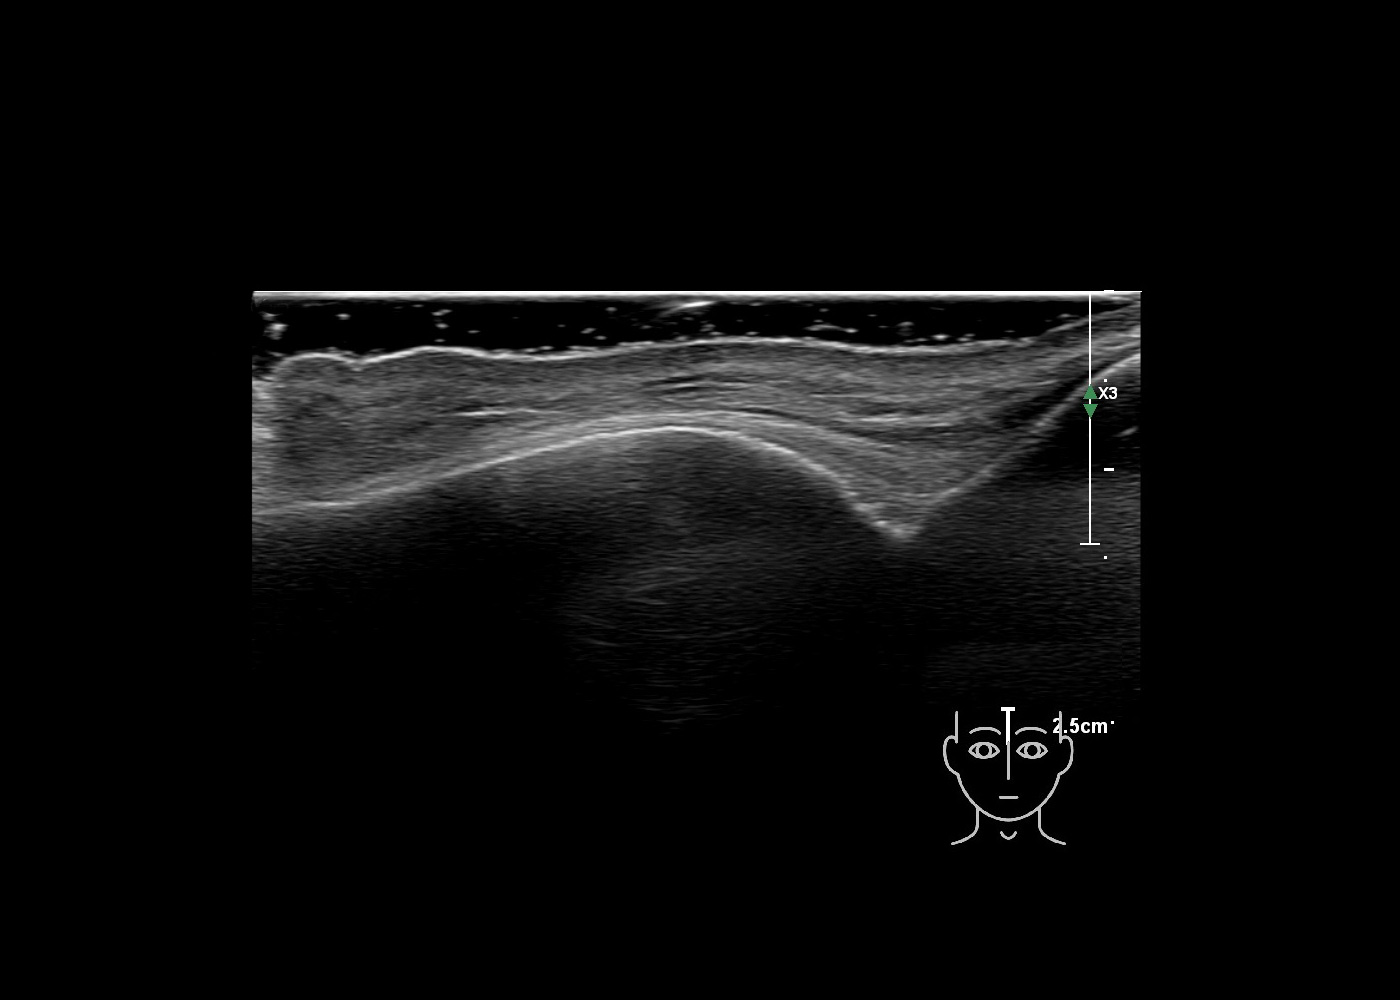

In this section you will learn more about the different layers of the face with the use of ultrasound. When you click on the secondary ultrasound image, you will see the different structures as an overlay. This will help to train yourself to recognize the different layers of the face.

Study the first image to recognize the different layers. If you are sure about the layers, swipe to the second image to view the answer (if applicable).